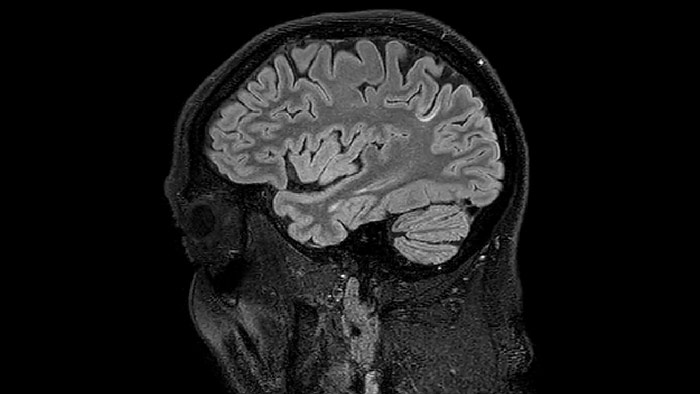

He says the accelerated scanning is achieved via the use of Compressed SENSE and MultiBand SENSE. “We can use Compressed SENSE acceleration factors of about 10 on a 3D FLAIR for instance, which is quite remarkable compared with what we saw with the Achieva. With 3D FLAIR, we can push the spatial resolution to 0.3 cubic mm and it works. Previously, our 3D FLAIR scans lasted about 8 minutes, but now with Elition they are five minutes. The SNR is also visibly better. Our SWI and QSM scans look fantastic. Also, since a lot of neuroimaging is EPI based, using the MultiBand SENSE technique can increase temporal resolution and make it possible to run complicated DTI scans relatively quickly.”

Juxtacortical MS lesion elition

Sagittal 3D FLAIR with 0.3 mm3 voxel volume acquired in 5:12 min. using Compressed SENSE showing a (juxta)cortical MS lesion.